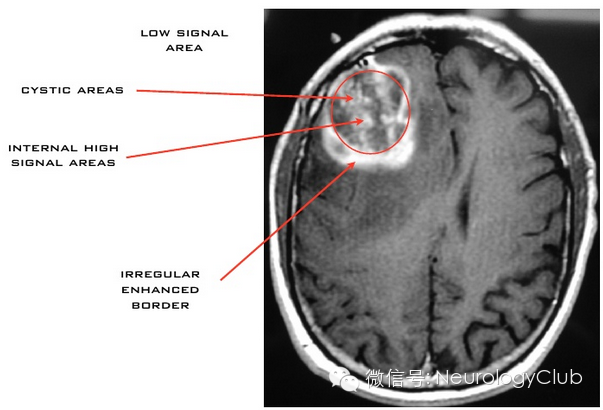

CT显示肿瘤呈边界不清的混杂密度影,常见瘤内出血所致高密度或囊性变、坏死;肿瘤跨胼胝体生长至对侧大脑半球时,呈“蝴蝶征”,水肿和占位效应明显。MRI在一定程度上能够揭示肿瘤的病理改变:T1WI呈不均匀低信号(图 1a),多合并坏死、囊性变或出血性改变;T2WI呈混杂高信号,中心坏死区为高信号,肿瘤生长区周围呈等信号,部分病变与肿瘤周围水肿分界不清,肿瘤内异常血管增生形成线样“流空效应”区(图 1b)。增强扫描肿瘤边缘呈显著对比强化,呈“花环”(ring/rim-enhancing)样(图 1c)、不规则环形、岛形或螺旋形改变;囊变性和坏死区周围肿瘤实质呈特征性“假栅栏征”,即圆形、椭圆形未强化区散在分布在强化区内,类似乳突蜂窝小房。DWI多呈高信号,ADC值明显减低。MRS提示NAA峰降低,Cho升高明显,MI峰较低级别星形细胞瘤低。灌注成像显示,病灶周围和病灶内有多处高灌注区(图 1d),提示大量肿瘤血管生成。胶质母细胞瘤虽具典型影像学特征,但仍需注意与颅内单发转移瘤、间变性胶质瘤、淋巴瘤等肿瘤性病变,以及脑脓肿、结核瘤、脱髓鞘假瘤等非肿瘤性占位性病变相鉴别。

(图7:MRI增强肿瘤呈混杂信号)